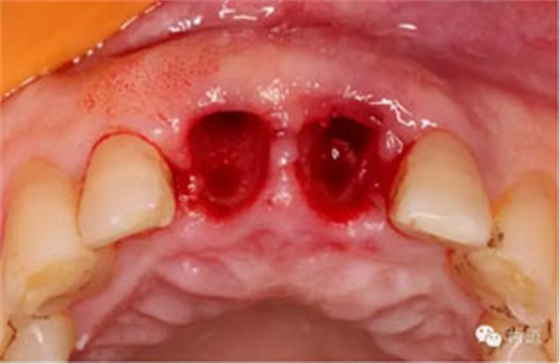

拔牙窩

探查唇側(cè)骨板(約齦下3-4mm)